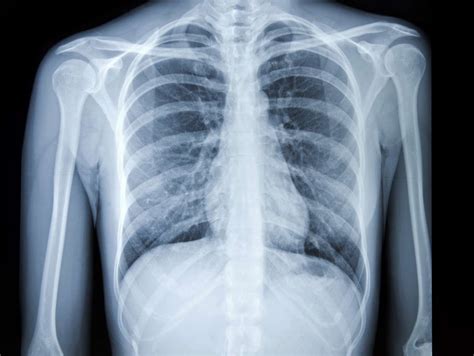

1. Chest X-ray

Chest X-ray

A chest X-ray is a standard test used to examine the lungs and surrounding structures. It helps detect abnormalities such as pneumonia, tuberculosis, and lung tumors.